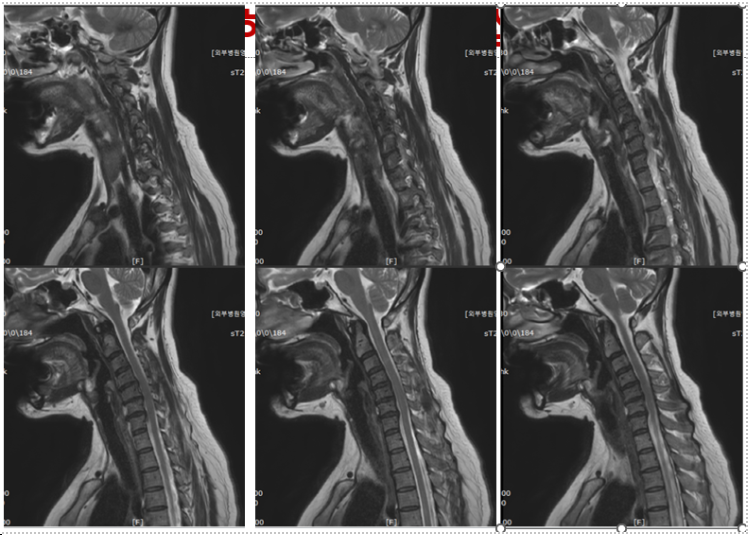

경추부 방사선촬영 상에서는 측만과 전만소견 그리고 추간판의 간격이 좁아진 소견을 보였으며, 경추 MRI 검사상 목디스크 소견을 보였습니다. 손저림 때문에 뉴론틴이라는 약을 2달정도 복용을 하고 있었으나 별 효과는 없었습니다.